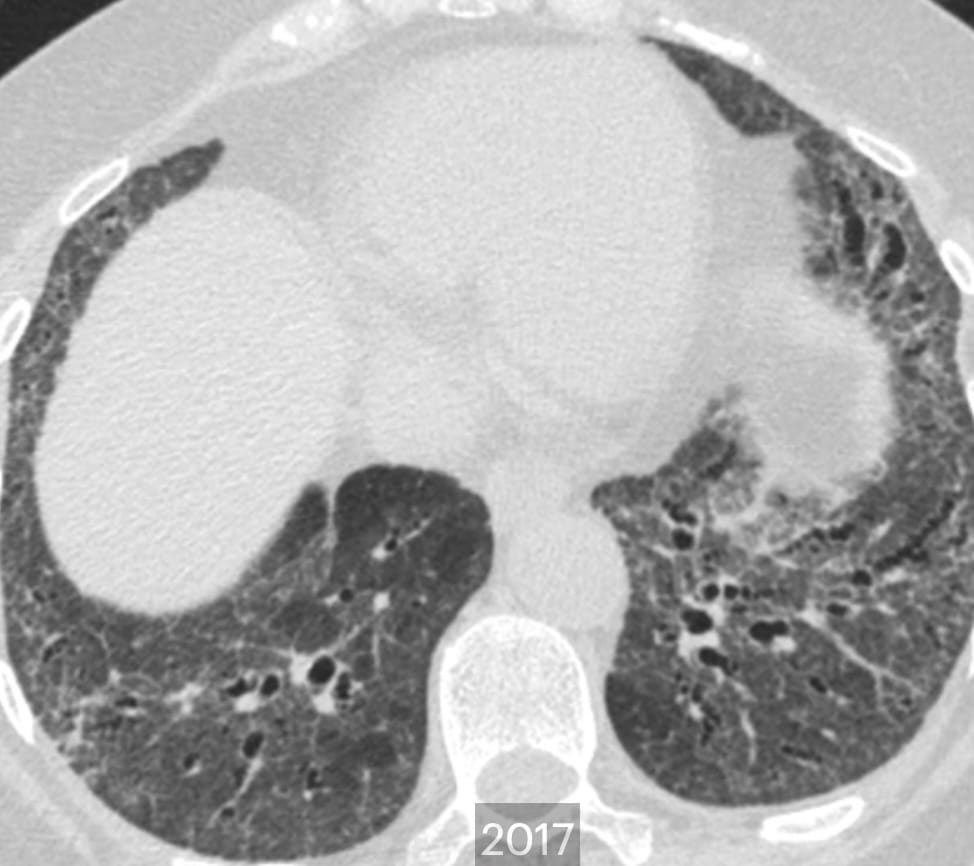

- Fibrotic Hypersensitivity Pneumonitis